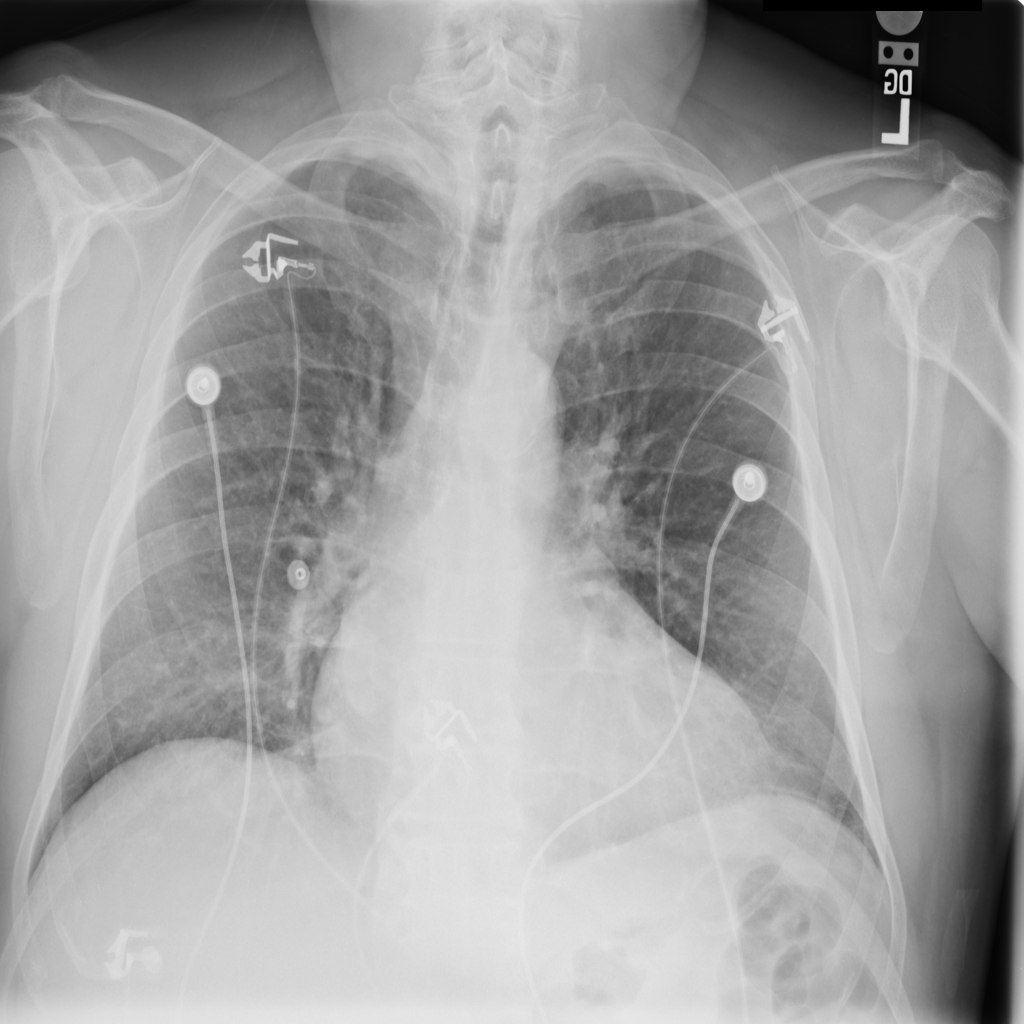

Cardiomegaly

Cardiomegaly means the heart appears enlarged on the chest X-ray. It is a descriptive imaging finding that can be related to heart strain, chronic pressure or volume changes, or even projection effects.

Showing up to 90 reference images for Cardiomegaly.

PAT-F3E7 · IMG-000Cardiomegaly

PAT-F3E7 · IMG-000

PA